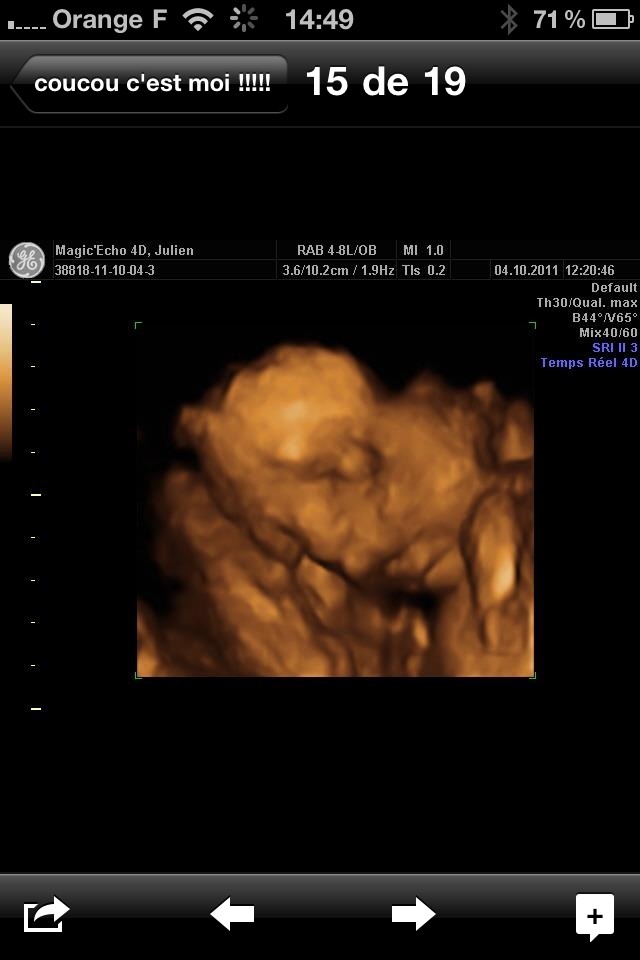

Quand je les avaient contacté ils mon dit c'est la bonne période bebe est pas trop gros

J'avais fait pareil pour Julien j'étais a 22 sa aussi